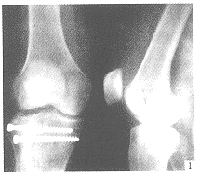

Schatzker将胫骨平台骨折分为6型(图1)。

Ⅰ型:外侧平台的单纯楔形骨折或劈裂骨折。 医学百科网 | YxBaike.Com

Ⅱ型:外侧平台的劈裂压缩性骨折。 医学百科网 | YxBaike.Com

Ⅲ型:外侧平台单纯压缩性骨折。

Ⅳ型:内侧平台骨折。其可以是劈裂性或劈裂压缩性。 医学百科网 | YxBaike.Com

Ⅴ型:包括内侧平台与外侧平台劈裂的双髁骨折。

Ⅵ型:同时有关节面骨折和干骺端骨折,胫骨髁部与骨干分离,即所谓的骨干-干骺端分离,通常患者有相当严重的关节破坏、粉碎、压缩及髁移位。 医学百科网 | YxBaike.Com